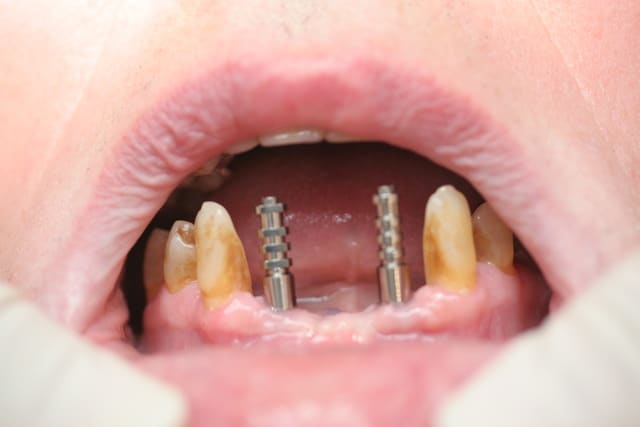

Pxav, faut changer de fil...

Là, ton truc sur implants, c'est bien de voir quelques choses de différents !

T'aurais pas du placer les implants si lingual !

;-))

C'est drôle, j'ai fais un truc du genre hier (plus simple)